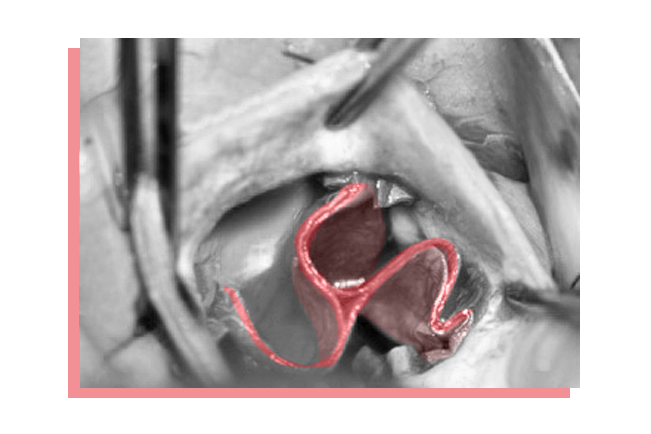

Mit diesen schonenden Eingriffen lassen sich inzwischen die meisten Fehler an der sogenannten Mitralklappe in der linken Herzhälfte und der Aortenklappe behandeln. In den letzten Jahren entwickelten Lange und sein Team zudem Techniken für Herzklappen-OPs, bei denen der Brustkorb vollständig unversehrt bleibt. Dabei führen sie ihre Instrumente zum Beispiel über die Leiste ein. Doch nicht immer sind minimalinvasive Herzklappen-OPs möglich, etwa bei der sehr seltenen Ebstein’schen Anomalie. Doch Lange ist einer von nur wenigen Ärzten weltweit, die diesen angeborenen Fehler an der Trikusspidalklappe korrigieren können, ohne die Klappe ersetzen zu müssen.

Herzklappen funktionieren wie Schleusen. Sie öffnen und schließen sich mit jedem Herzschlag und sorgen dafür, dass das Blut immer in die richtige Richtung fließt: aus dem Vorhof in die Herzkammer und von dort in den Rest des Körpers. Jede Herzhälfte hat zwei dieser Klappen.